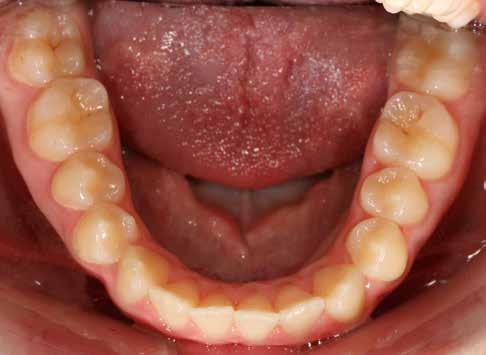

Ebben a cikkben egy 16 éves lánypáciens esetét szeretném bemutatni (1–7. képek)

A Pitts21-es fix készülékes kezelés során a harapásemelőket a felső nagyőrlő fogakra ragasztottuk, hogy a felső molárisok intrúziójával segítsék a harapás zárását (8. kép) Ún. keresztharapásos, majd később normál class 2-es gumihúzással (9–10. képek), továbbá az elülső fogakon alkalmazott ún. Rainbow harapás-záró gumihúzással (11. kép) korrigáltuk a jobb oldali teljes premolárisnyi distal-harapást, valamint az elülső nyitott harapást.